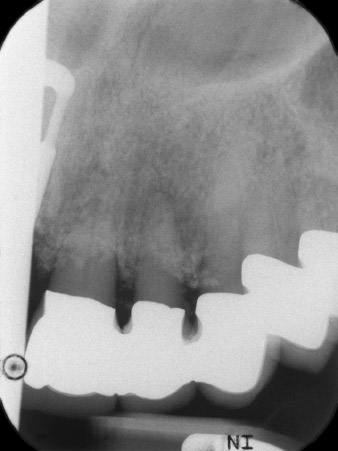

La radio a révélé une perte osseuse horizontale autour des dents 21 et 22 (Fig. 1). Lorsque la structure de couronne a été retirée, ces dents ont involontairement été extraites en même temps.